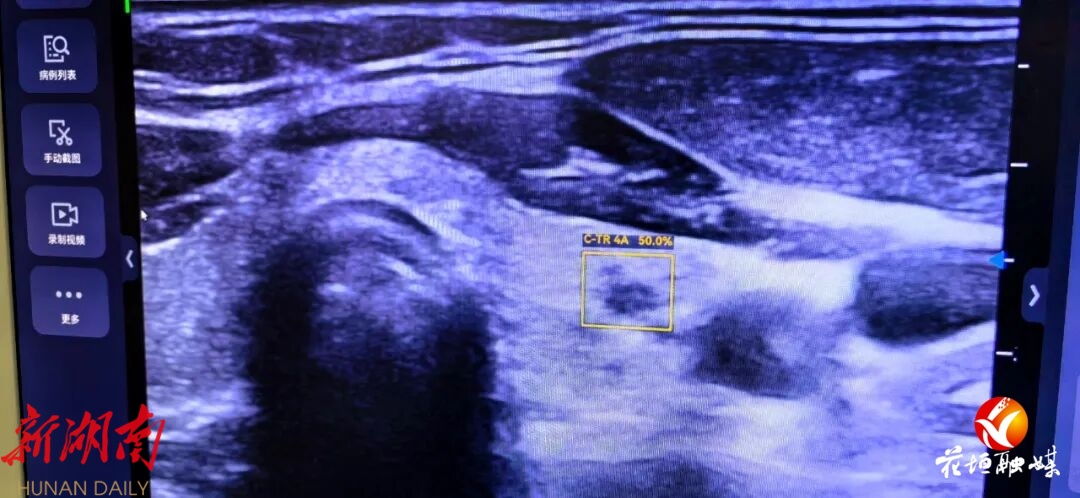

为患者使用AI系统实时分析超声图像检查中

黄色框内为AI检查出的病灶